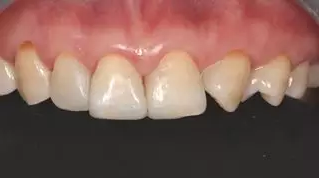

術前上前牙正面照

病例分享|復合樹脂微創(chuàng)美學修復關閉上前牙間隙